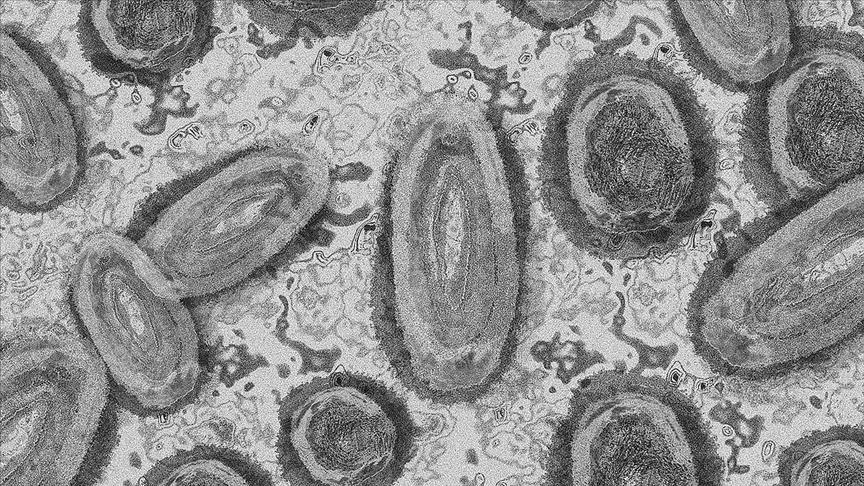

Sudan on Sunday confirmed its first monkeypox case.

Monkeypox is a virus that causes disease with similar but less severe symptoms to smallpox, including a fever, rash and swollen lymph nodes.